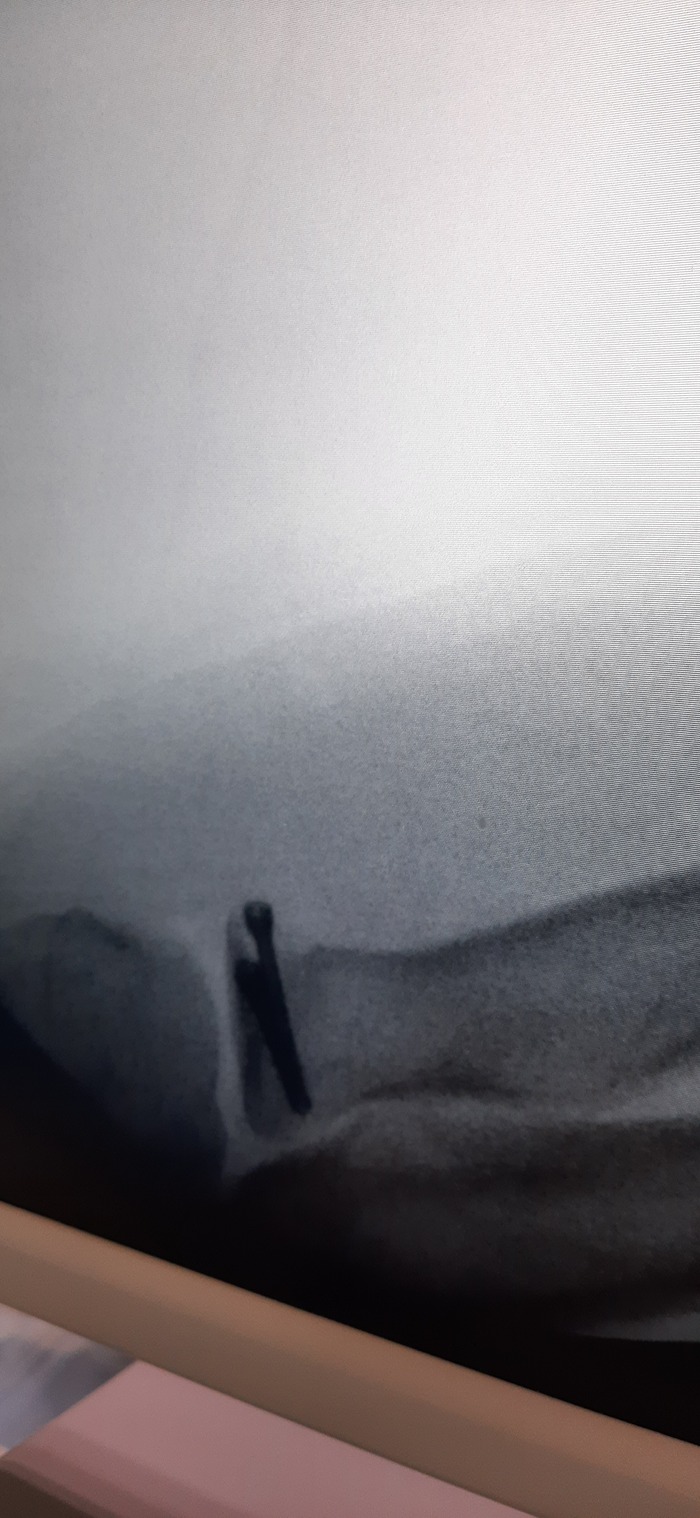

Ну и очень много рентгеновских снимков